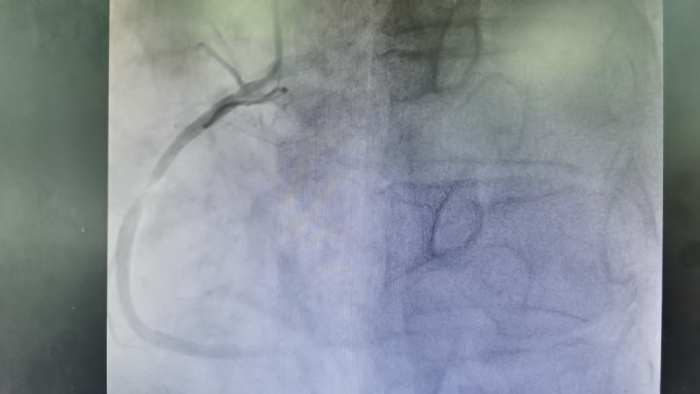

心血管内科一病区医生评估病情后考虑郭先生为急性冠脉综合征,并告知病情,说明冠状动脉介入检查的目的及意义,郭先生于当天21:17分在医护的陪同下,到介入室行冠状动脉造影检查评估。

检查提示郭先生右冠中段95%狭窄,血管病变“命悬一线”评估病情危重,随时进展至急性心肌梗死,已达到冠状动脉支架植入指征,但因为郭先生是外省前来桂林旅游的特殊身份,无陪同家属,下一步治疗方案无法进一步开展,手术医生张羽中立即将情况汇报给在隔壁手术间做心脏介入手术的心血管内科一病区主任林创标,林主任得知病情及郭先生的特殊情况后,立即决定启动急诊救治应急预案。

科室主任及总值班主任联合签署同意后,22:04分手术医生张羽中及助手医生董振锦开始为患者行冠状动脉支架植入手术治疗,手术过程顺利,22:23分手术顺利结束,术后第一时间告知了郭先生家属情况,报告平安,家属对二附院医生表示感谢。